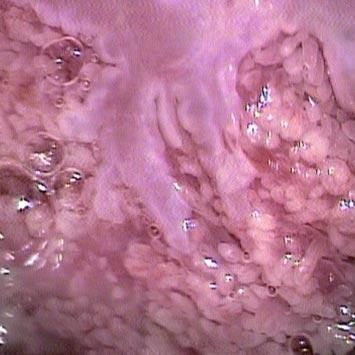

Realiza desde hace más de 30 años estudios como la toma de Papanicolaou, Colposcopía, Microcolposcopía. Y para casos especiales, la microcolposcopía o toma de biopsias dirigidas; siempre con el profesionalismo y calidad que lo caracteriza.

En caso de que lo requiera, también realiza histeroscopia y diagnóstico para detección temprana de cáncer en endometrio.

El Dr. Víctor Martín Ralda Gómez cuenta con equipos de última tecnología como videocolposcopio con imágenes digitales y equipos de radiofrecuencia, además de equipos de crioterapia, equipos de láser de CO2 y microcolpohisteroscopio.